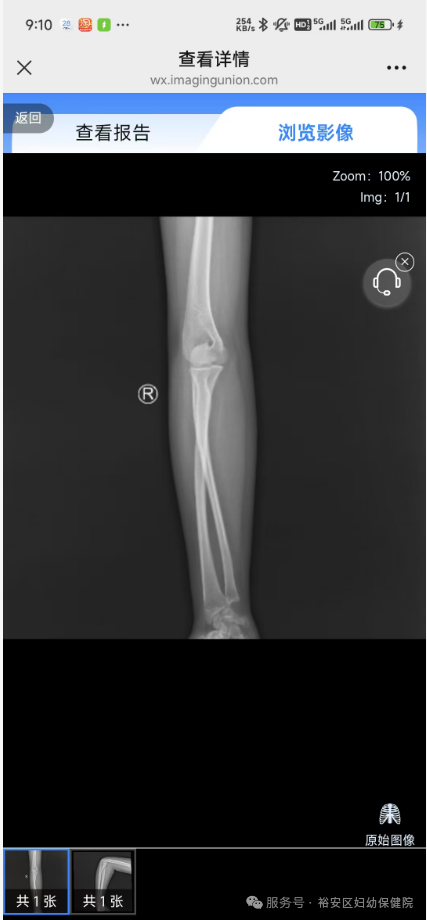

数字影像服务是指医疗机构在进行CT、MRI、CR、DX等影像检查时,将患者诊断报告及符合DICOM标准的原始图像储存并连通到影像云平台上,患者可以通过扫描医院提供的影像报告单上的二维码,不限定次数浏览、分享及下载。授权的医疗机构可以在本地医生工作站调阅患者的外院影像图片和报告。

患者通过扫描影像报告单上二维码可随时不限次数地查阅影像,省去了携带传统塑料胶片的烦恼,同时可以随时将检查结果和原始图像实时分享给亲朋或转诊分享给医生,朋友和医生都可通过手机和电脑以及平板设备查看患者原始图像。无需刻录光盘,携带方便。可以保存当次影像检查,影像资料。门诊患者保存15年,住院患者保存30年,再也不用担心影像丢失和损坏。